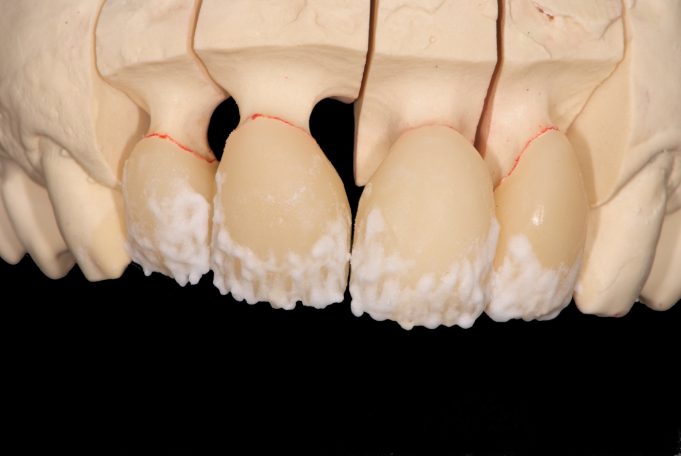

Metallfreie Frontzahnkronen mit individueller keramischer Verblendung.

Virtuelle Planung mit Vorab-Provisorium aus dem Labor.

Frontzahnkronen Oberkiefer neu zur Verbesserung der Ästhetik.